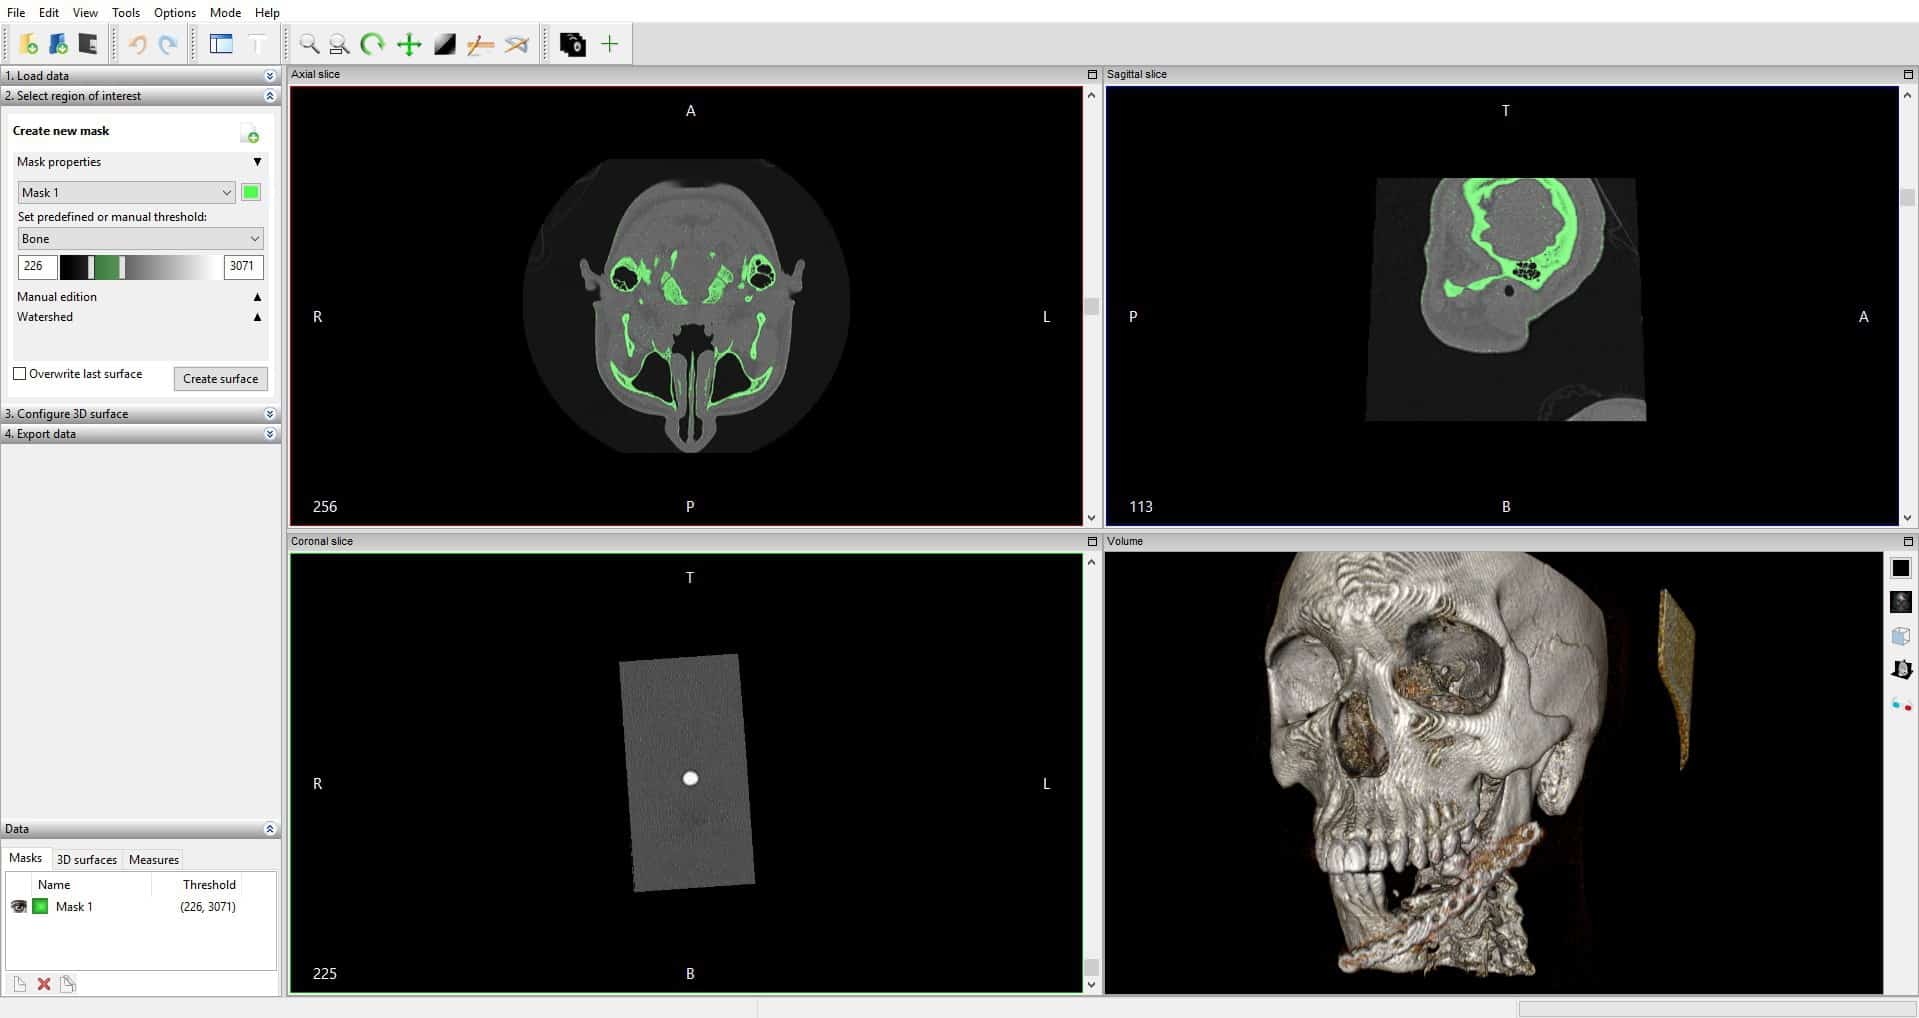

Лазерная камера для печати медицинских изображений на пленке стандарт dicom